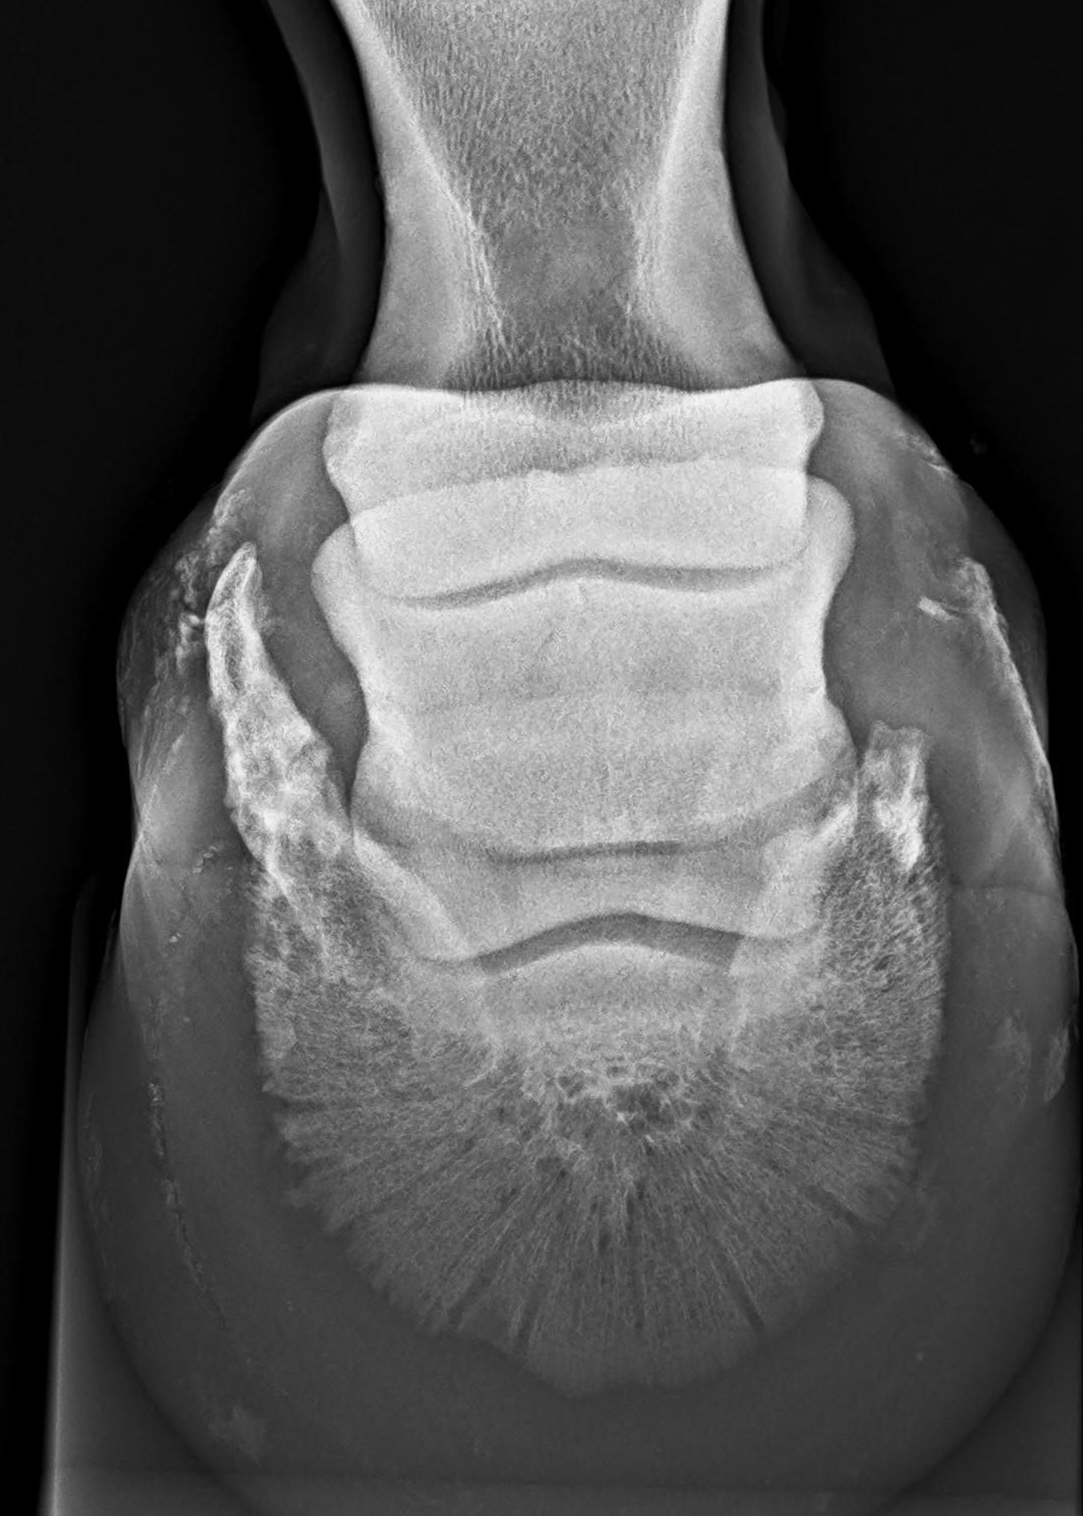

Met een röntgenologische keuring brengen we het skelet in beeld. Hiermee verkrijgen we een overzicht van eventuele OC(D), cystes, artrose, kissing spines, et cetera. Dankzij extra zware kwaliteit röntgenapparatuur, kunnen ook goede foto's van hals en rug worden genomen.